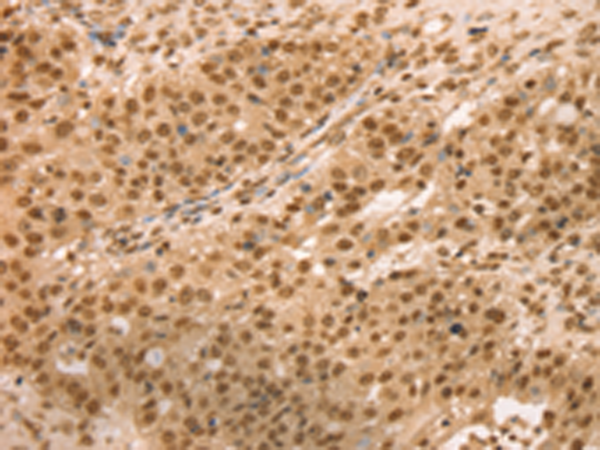

分类: 科研抗体货号: P01830别名: Mvp1应用: WB,IHC反应种属: Human, Mouse

分类: 科研抗体货号: P01824别名: SNO; SnoA; SnoI; SnoN应用: WB,IHC反应种属: Human, Mouse

分类: 科研抗体货号: P01821别名: SNAP-23; SNAP23A; SNAP23B; HsT17016应用: WB,IHC反应种属: Human, Mouse, Rat

分类: 科研抗体货号: P01882别名: TCFEB; BHLHE35; ALPHATFEB应用: WB反应种属: Human, Mouse

分类: 科研抗体货号: P01906别名: CC3; TIP30; SDR44U1应用: WB反应种属: Human, Mouse

分类: 科研抗体货号: P01874别名: EBI; TBL1; SMAP55应用: WB,IHC反应种属: Human, Mouse

分类: 科研抗体货号: P01903别名: RNF9; HERF1; RFB30应用: WB,IHC反应种属: Human

分类: 科研抗体货号: P01868别名: TAF2I; PRO2134; TAFII28; MGC:15243应用: WB,IHC反应种属: Human, Mouse, Rat

分类: 科研抗体货号: P01898别名: AFP; RNF95; ZNF173应用: WB,IHC反应种属: Human, Mouse, Rat

分类: 科研抗体货号: P01859别名: slp5应用: IHC反应种属: Human, Mouse, Rat